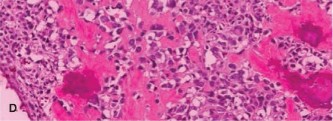

Which of the following histopathologic slides (Fig. 8–24A–D) is most consistent with osteosarcoma?

Figure 8–24 C–D

The correct answer is slide (D). Histologic examination of osteosarcoma reveals “lace-like” pink osteoid formed by malignant osteosarcoma cells. The degree of pleomorphism and atypia is considerable. Areas of necrosis with few viable cells (if any) are often seen.